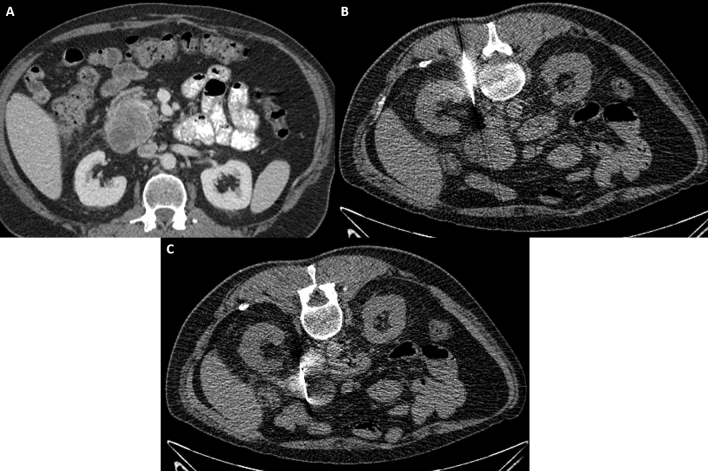

Fig. 2.

43-year-old male with suspected enhancing pancreatic head mass diagnosed on CT A during the COVID-19 pandemic with no availability of endoscopy facilities. CT-guided biopsy images B and C demonstrate a posterior pararenal approach with successful targeting and biopsy of the pancreatic head lesion

Fig. 3.

55-year-old male with history of Roux-en-Y gastric bypass suspected pancreatic head mass and superior mesenteric vein thrombosis status post failed endoscopic biopsy (A). CT-guided biopsy image B demonstrates successful pancreatic biopsy utilizing an anterolateral approach, avoiding adjacent bowel and the thrombosed superior mesenteric vein

Fig. 4.

49-year old male with suspected pancreatic body adenocarcinoma A status post negative endoscopic biopsies. CT-guided biopsy image B demonstrates a successful lateral approach with the patient in a slightly oblique position, allowing for displacement of the colon and small bowel along the needle tract